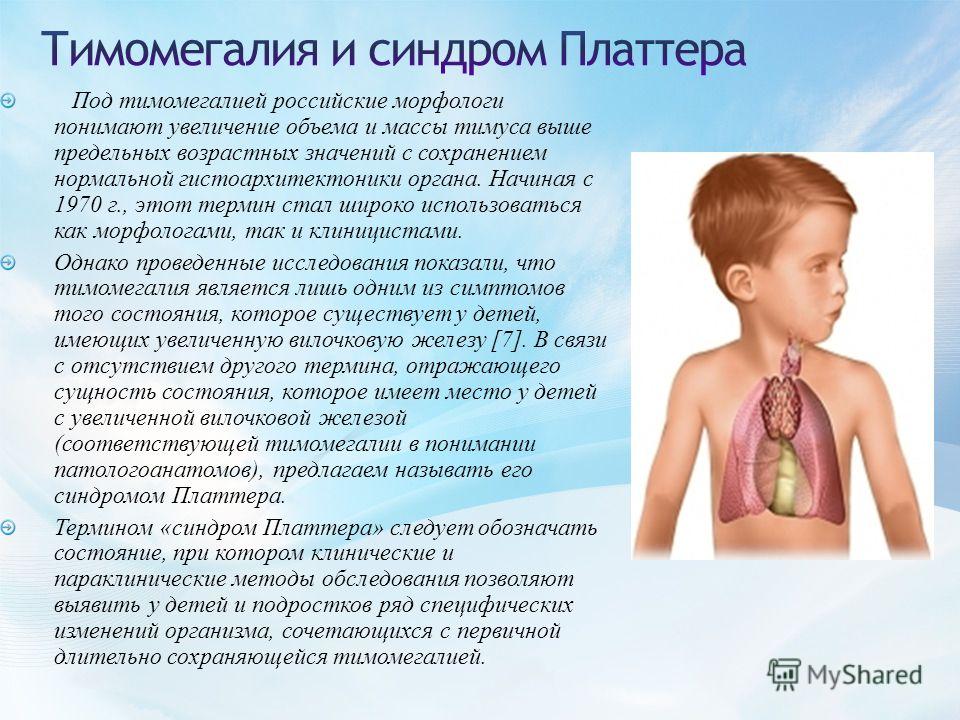

Тимомегалия: что это такое и как проявляется

Раздел: Фотоальбом решений